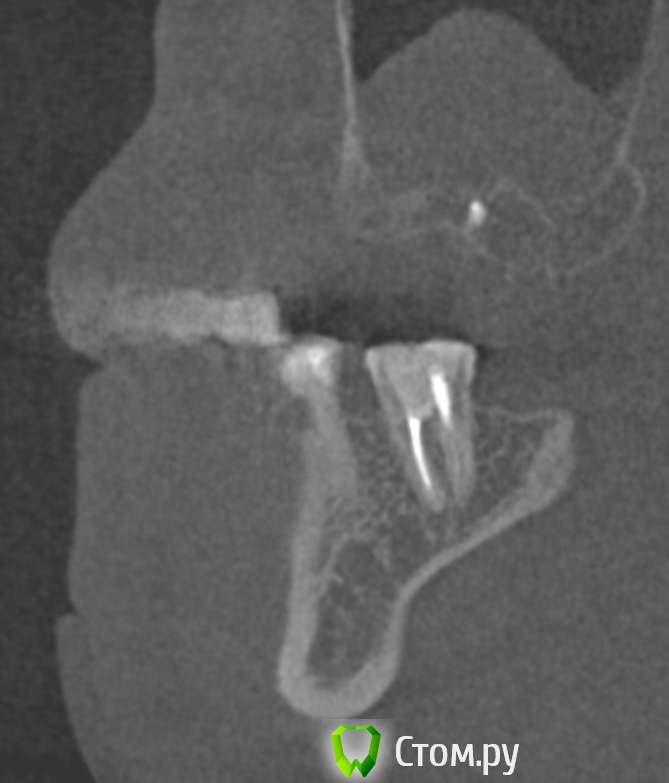

dr-krasnov Опубликовано 10 июня, 2014 Поделиться Опубликовано 10 июня, 2014 Добрый день. На томограмме ретенционная киста слева, одонтогенный синусит справа, замыкательная кортикальная пластина в области корня уже отсутствует. (желтые стрелки) С моей точки зрения необходимо эндоперелечивание причинного зуба. К лору можно сходить за рекомендациями по поводу ретенционной кисты. Обычно с ними ничего не делают, пока они не беспокоят. 1 Ссылка на комментарий

dr-krasnov Опубликовано 10 июня, 2014 Поделиться Опубликовано 10 июня, 2014 (изменено) Тэкс, посмотрел КТ. Претензий к лечению зуба не имею. 4й канал найти не удалось. То был ограниченный артефакт от запломбированного канала. Связи между этим зубом и реакцией слизистой скорее всего нет. Да и синусита нет. Изменения слизистой скорее имеют гиперпластическую природу. Источником исходных реакций послужили уже отсутствующие зубы. Архивные снимки расставили бы все точки над и. Несколько картинок: Небный на осях, можно придраться к незначительному расширению периодонтального пространства апикально, но я бы не стал http://s018.radikal.ru/i515/1406/b8/d712dd4f6158.jpg Дистальный щечный http://s020.radikal.ru/i710/1406/4f/990608ed482a.jpg Мезиальный щечный http://s018.radikal.ru/i518/1406/52/534d8d8534ec.jpg В общем, признаков периодонтита не вижу, рентгенологических показаний для резекции тоже.Я бы порекомендовал динамическое наблюдение. Изменено 10 июня, 2014 пользователем dr-krasnov 1 Ссылка на комментарий